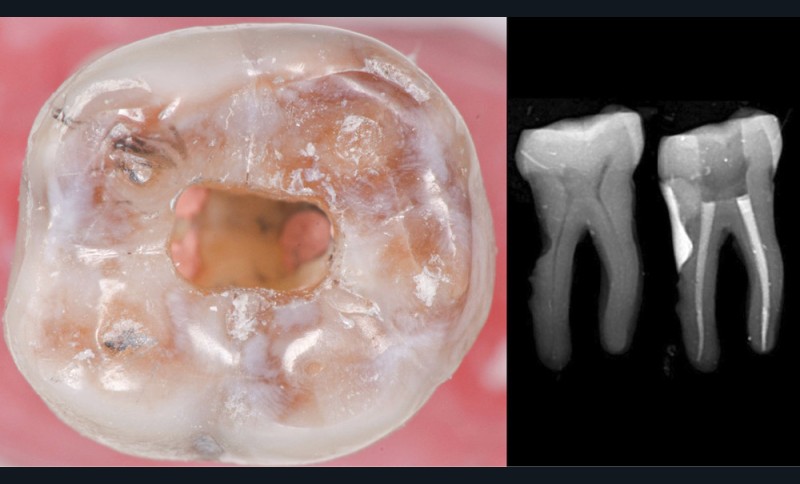

Une cavité d’accès trop petite [2] optimiserait le pronostic biomécanique (préservation dentaire maximale) mais pourrait compromettre le pronostic endodontique : mauvaise lecture de l’anatomie, instrumentation partielle, non ergonomique et avec risque de fracture, défaut de nettoyage des parois canalaires [3], irrigation inadéquate, difficulté d’obturation canalaire, voire d’obturation coronaire. Ce sera le cas des cavités d’accès « Ninja » [4] ou ultraconservatrice (fig. 1), des cavités d’accès « Truss » [5] (fig. 2), des cavités d’accès dites « opportunistes » [6] (fig. 3).

Une cavité d’accès trop large optimiserait le pronostic endodontique mais compromettrait le pronostic biomécanique. C’est le cas de la cavité d’accès traditionnelle, qui a longtemps été « au service » du praticien réalisant le traitement canalaire (dentist-centered dentistry ou dentisterie centrée sur le praticien). Les étapes d’instrumentation, d’irrigation et d’obturation étaient ainsi facilitées grâce à des accès visuel et instrumental exagérés, aux dépens de structures dentaires saines (fig. 4).